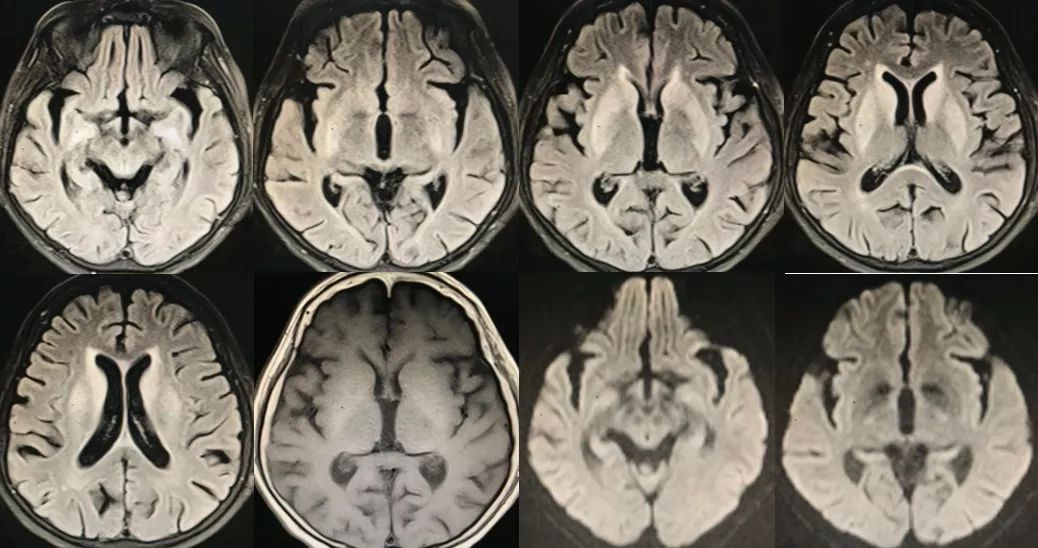

女,63 岁,反复头晕、四肢乏力、记忆力下降5年。

答案 :伴有皮层下梗死和白质脑病的常染色体显性遗传性脑动脉病(CADASIL)

本病例比较典型,绝大多数老师回答正确。CADASIL主要累及侧脑室周围和深部白质。以额叶白质最常受累,其次为颞叶和顶叶,而枕叶受损程度相对较轻。外囊、颞极的对称性异常信号对诊断有高度提示作用。胼胝体亦可全层受累,引起胼胝体萎缩。当然也有不典型CADASIL,表现为脑小血管病,如微出血、脑萎缩等。可以通过ADASIL量表进行筛查,如果总分≥15分者,提示CADASIL。